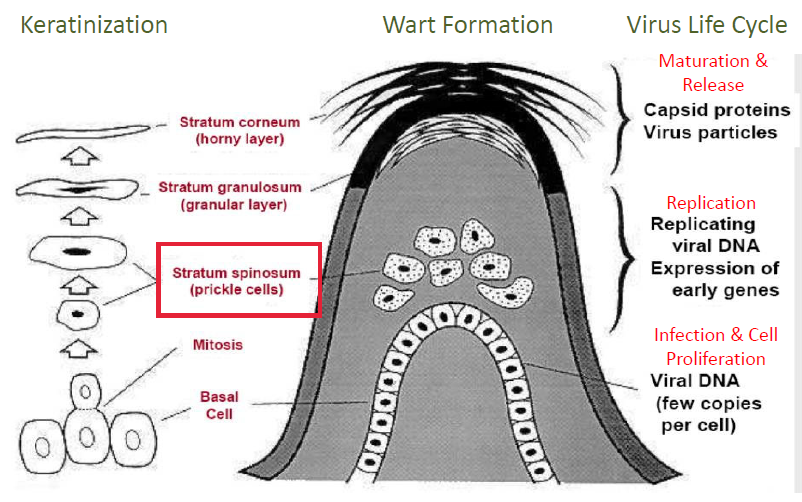

Papillomaviruses

- 在表皮(1-4)、黏膜 (genital:6, 11)

- 接觸傳染

- dysplasia (不典型增生)

- Warts (疣)

- Cervical cancer (子宮頸癌)

- 促進 keratin (角蛋白) 產生 → epithelial spikes (papillomatosis)